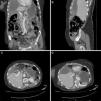

TAC coronal (A) y sagital (B) en los que se observan los hallazgos descritos, así como imágenes hiperdensas en el interior de la vesícula que podrían corresponder a la capa interna de la pared necrótica y desprendida. Corte axial de TAC en fase venosa (C) en el que se observa la torsión de la vesícula sobre su hilio (flecha blanca), con una lengüeta de líquido perivesicular, pared hipercaptante y una imagen litiásica en su interior. El corte axial de la imagen D muestra la posición anómala de la vesícula y la impronta que ejerce sobre la superficie hepática.

Caso clínicoPresentamos el caso de una mujer de 78 años que acudió al servicio de Urgencias por dolor constante en hipocondrio derecho de 3 días de evolución, sin episodios similares previos. No asociaba vómitos, coluria, ictericia ni dolor de características pleuríticas. No refería fiebre, astenia ni síndrome constitucional asociado. La paciente se encontraba hemodinámicamente inestable, con hipotensión arterial, taquicardia y oliguria, estabilizándose tras 1,000 cc de fluidoterapia. Permaneció afebril en todo momento. La exploración física reveló dolor en el hipocondrio derecho y signo de Murphy positivo. La analítica evidenció leucocitosis de 19,000g/dl, con desviación izquierda (90% neutrófilos), normalidad en el perfil hepático y la tomografía axial computada (TAC) con colelitiasis, pared vesicular irregular y múltiples focos de discontinuidad asociada a una colección perivesicular hepática anterior que se extendía hacia el espacio subfrénico derecho con realce peritoneal, indicativa de colecistitis aguda litiásica perforada (fig. 1).